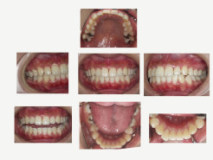

初診時より、約1年後の口腔内写真。 歯間乳頭の改善。全体的に赤みも取れ健全 な状態を維持できている。 その後、定期健診も継続されている。 |

約3年経過後の口腔内写真。 経過は良好で、プラークコントロールも維持できている。 |